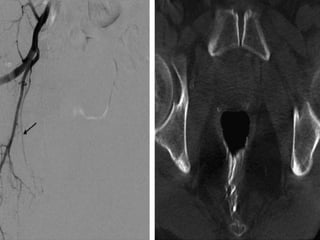

The prostate gland is a pyramid-shaped organ that weighs approximately 20 grams and measures 3x4x2 cm. It has three zones - the peripheral zone (70%), central zone (25%), and transitional zone (5-10%). Prostate cancer develops in the peripheral zone, while benign prostatic hyperplasia (BPH) develops in the transitional zone. The prostate receives its blood supply from various arteries, most commonly the internal pudendal artery (34%). Knowing the detailed arterial anatomy is important for procedures like prostate artery embolization (PAE) to treat conditions like BPH and prostate cancer. Imaging tools like CT angiography and cone beam CT can help the interventional radiologist map the arterial supply before